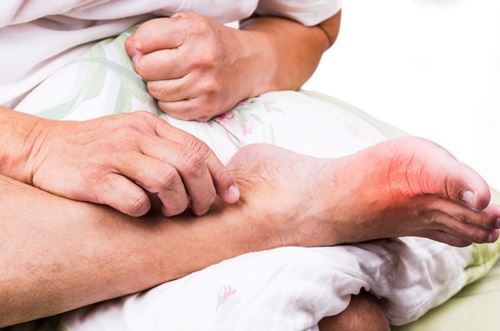

Romatizmal hastalıklar toplamda zannedildiği gibi sadece yaşlılarda görülmez. Her yaş grubunda baskın olarak görülen romatizmal bir hastalık vardır. Ankilozan spondilit 25-45 yaş arasında sık görülürken, Romatoid artrit 30-50 yaş arasında daha sık görülür. Lupus genellikle 15-40 yaşlar arasında ortaya çıkarken, Gut 50 yaşın üzerinde kendini gösterir. Artroz dediğimiz kireçlenme durumları ise 55 yaşın üstündeki bireylerde sık görülür. Yine benzer şekilde romatizmal hastalıklar sadece kadınlarda görülmez. Erkeklerde sıklıkla rastlanan romatizmal hastalıklar da vardır. Romatoid artrit ve Lupus kadınlarda sık görülürken, Gut hastalığı erkeklerde daha sık görülmektedir.

1- İltihaplı romatizmal hastalıklar: İltihaplı romatizmalar birkaç sebeple gelişir. İlk sebep mikropların ekleme yerleşmesiyle (Stafilokok, Streptokok, Tbc basili gibi) gelişen romatizmal hastalıklardır. Genellikle yaşlılarda görülen bu tür, hastanede yatan bireylerde sıktır ve vücudun başka bir bölgesinden ekleme gelmektedir. Örnek verecek olursak hastanede zatürre tedavisi alan bir hastanın, belli bir süre sonra dizinde şişlik gelişmesi bir tür enfeksiyöz artriti akla getirmelidir. İkincisi, bağışıklık sisteminin bozulmasıyla gelişen mikropsuz iltihaptır. Bu tip iltihabın neden olduğu romatizmaların en önemlileri romatoid artrit (RA), ankilozan spondilit (AS), sistemik lupus eritematozus (SLE) ve yaygın bağ doku iltihabı yapan hastalıklardır (kollajen doku hastalıkları). Üçüncü iltihap tipi ise, başta ürik asit olmak üzere diğer kristallerin eklemlerde ve çeşitli dokularda oturarak yaptığı tahriş sonucu ortaya çıkan iltihaptır. Gut ve yalancı gut hastalığında bu tip bir iltihaplanma vardır. Bu tip romatizmaların tespitinde kan tahlilleri ve görüntüleme yöntemleri yardımcıdır.

- Gut Hastalığı